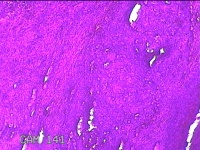

宫颈6点、12点组织

性别

女

年龄

57岁

临床诊断

子宫颈上皮内瘤变[CINⅢ级];子宫颈肿瘤

一般病史

阴道不规则出血1年。

标本名称

大体所见

1.“宫颈6点组织”:灰白粉红色组织1.3x0.8x0.3cm一块。 2.“宫颈12点组织”:灰白粉红色组织1.5x0.7x0.2cm一块。

图1